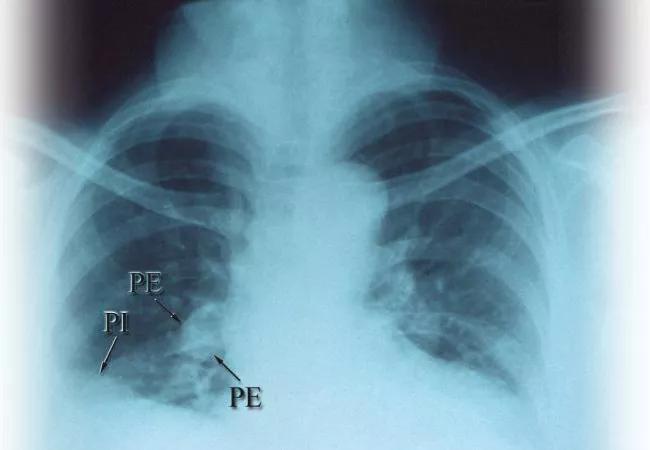

A fairly common patient presentation is of so-called unprovoked venous thromboembolism (VTE): development of a deep vein thrombosis or a pulmonary embolism without a clear provocation, such as major surgery or trauma.

Carrier and colleagues assigned more than 800 patients to undergo either limited occult-cancer screening (basic blood testing, chest radiography and age-appropriate screening for breast, cervical and prostate cancer) or limited occult-cancer screening in combination with an enhanced computed tomography (CT) abdominal scan that included a virtual colonoscopy and high-resolution pancreas imaging.